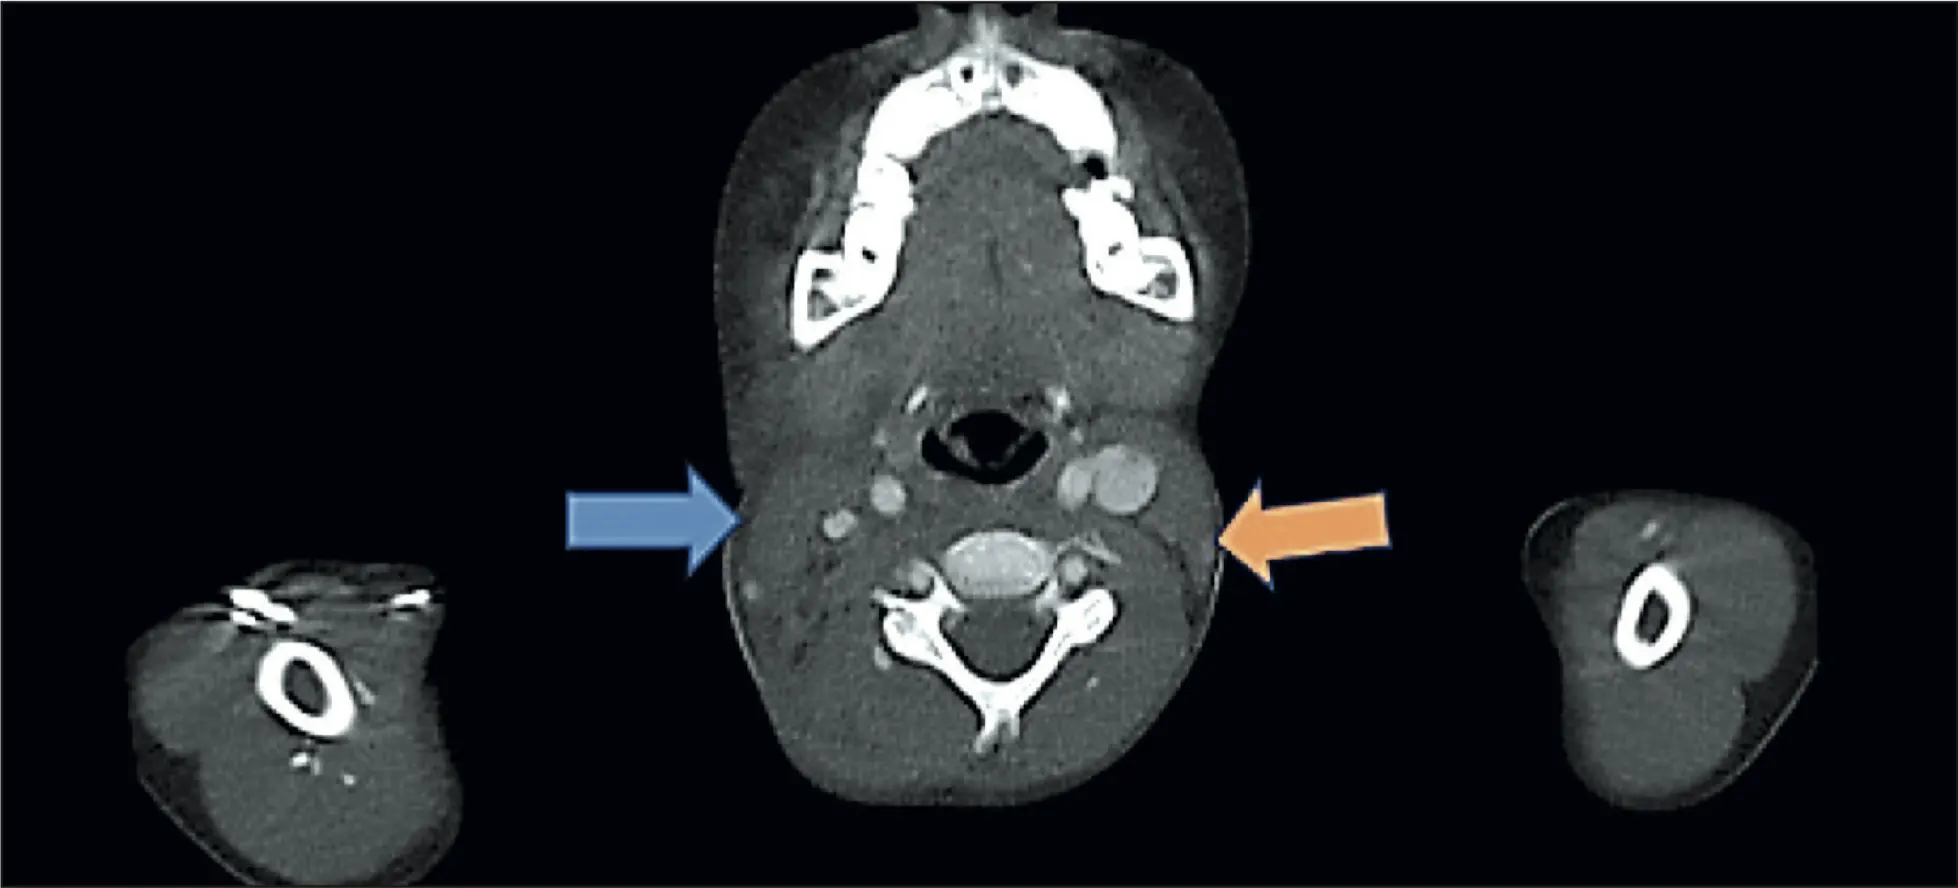

Tomografía de cuello, tórax, abdomen y pelvis

Imagen 3: Tomografía de cuello

Conglomerado ganglionar en hemicuello derecho que realza con contraste de forma heterogénea, impresiona infiltrar la parótida y esternocleidomastoideo de lado derecha, impresiona comprometer niveles ii, iii y iv derechos.

En lado izquierdo se evidencia adenopatías más visibles en nivel iii y iv

Adenopatías a nivel axilar bilateral y mediastino anterior y superior, impresiona masa mediastinal anterior

Adenopatías a nivel inguinal derecho